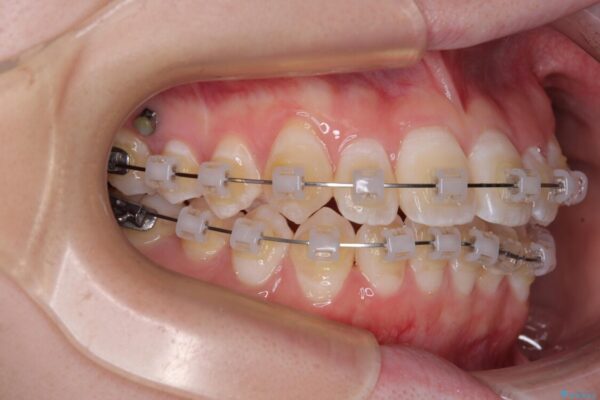

治療途中

• 【モニター】前歯のデコボコをスッキリ解消!目立ちにくいワイヤー矯正でスピーディに治療完了 治療途中画像

マウスピース矯正も検討されていましたが、「装着時間の自己管理が難しそう」「なるべく早く治療を終えたい」とのご希望から、ワイヤー矯正を選択されました。

目立ちにくさと費用のバランスを考慮し、プラスチックブラケット+メタルワイヤーを採用。日常生活でも装置の存在感を気にせずお過ごしいただけます。